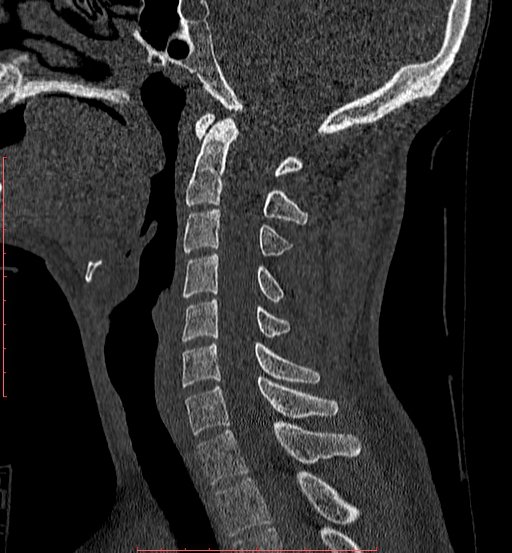

白色文字(排除指定关键词) Imaging Anatomy: interactive PACS-like atlas of radiological anatomy

解剖学模块